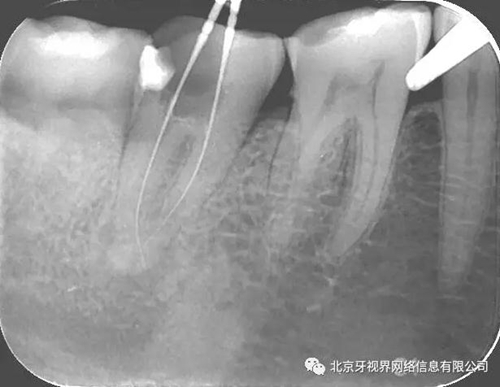

輔助檢查:15根尖周低密度影像,根尖1/3向近中彎曲

(1)15根尖周低密度影像結(jié)合查體診斷根尖周炎,根尖中下段明顯彎曲,能否疏通全長(zhǎng),順利抵達(dá)根尖區(qū)為術(shù)者首要考慮。

15備洞,揭頂,10#擴(kuò)大器預(yù)彎后疏通至全長(zhǎng),次氯酸鈉加超聲蕩洗,氫氧化鈣糊劑封藥,玻璃離子暫封,隨診。

2次復(fù)診常規(guī)根備加根充(AH-plus糊劑加牙膠尖根充)

2.如遇彎曲根管,建議多角度拍攝x線片,cbct首選

4.此例病例中,術(shù)前分析后,采取先解放其中上段后,10#擴(kuò)大器預(yù)彎緩慢前行,抵達(dá)根尖區(qū)。

最后附帶近期彎曲根管的圖片